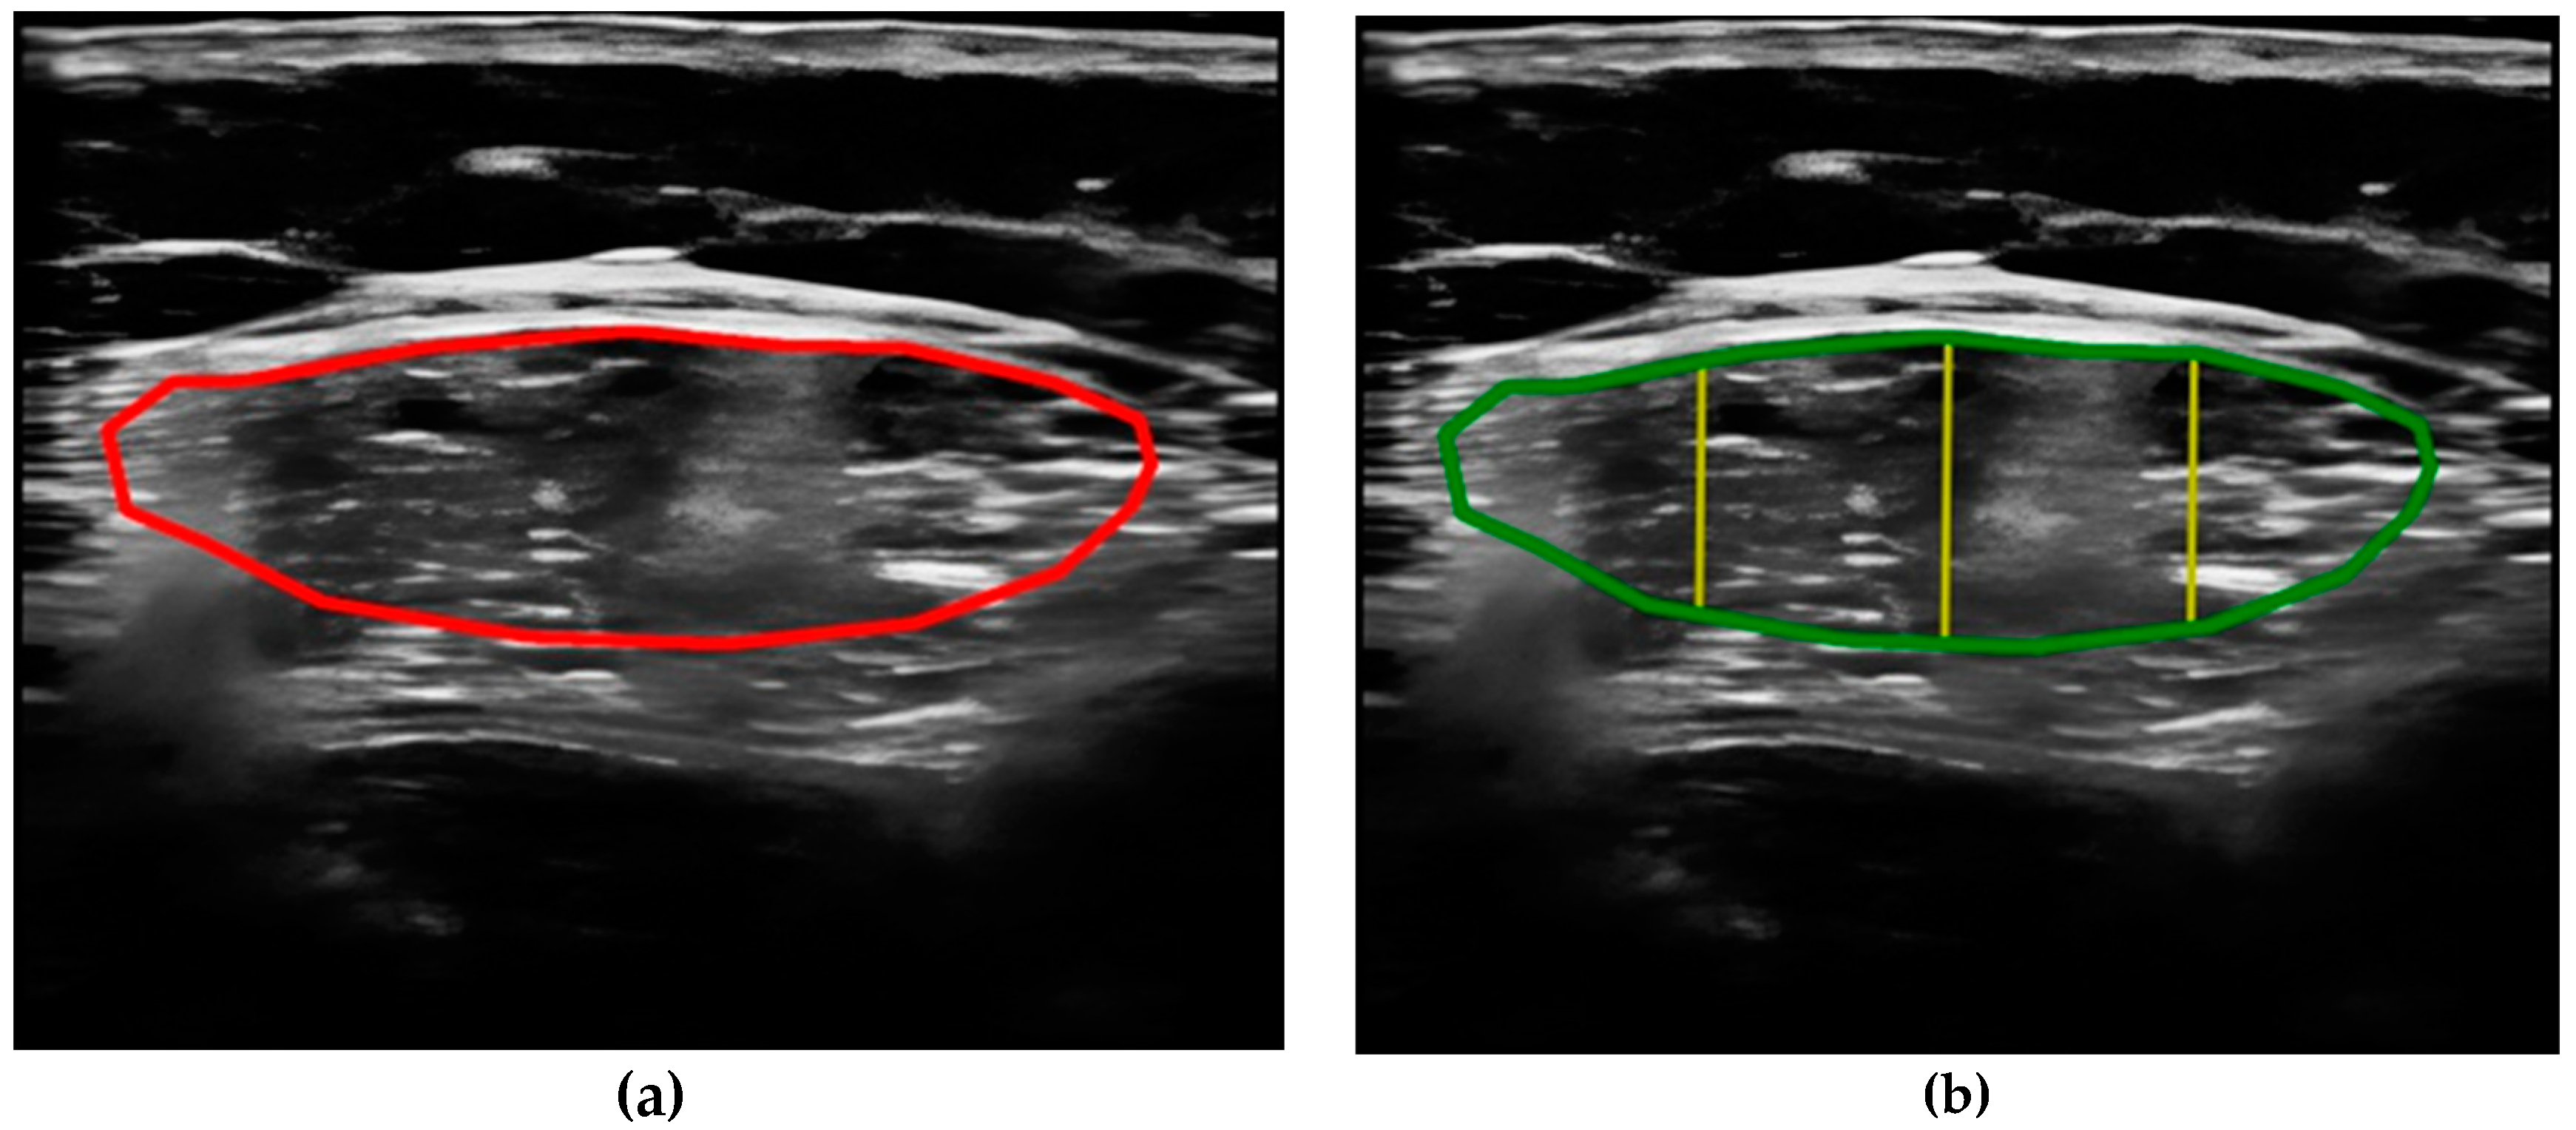

- Compare the measurements of the unilateral (right) RF of the patients performed by the expert evaluator (rater 1) using the standard tools included in the ultrasound image device (i.e., method A), see Figure 2, with those obtained by applying the PIIXMEDTM Ultrasound Imaging System (Dawako Medtech S.L., Valencia, Spain) (rater 2) (i.e., method B) [15,16,17,18,19] on the same acquired raw images, see Figure 3 and Figure 4.

Figure 2. (a) Acquired raw ultrasound image of the unilateral (right) quadriceps rectus femoris muscle in the transverse plane measure by rater 1 (i.e., method A); (b) Measurement of the variables by the conventional method using the ultrasound imaging device tools, by rater 1 (i.e., method A), for the parameters of the cross-sectional area, the Y-axis, i.e., transverse muscle thickness (MT), and the subcutaneous fat thickness (SFT).

Figure 3. (a) Acquired raw ultrasound image of the unilateral (right) quadriceps rectus femoris muscle in the transverse plane obtained by rater 1, scaled and automatically segmented (red color line) by PIIXMEDTM (rater 2—method B); (b) PIIXMEDTM processing (i.e., rater 2—method B) of the segmented transverse ultrasound image to obtain the results of CSA (green color), and MT (three yellow lines and their mean value) parameters.